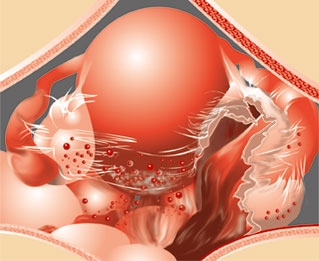

子宮内膜は月経のあと、卵巣から分泌される女性ホルモンの作用でだんだん分厚くなります。月経が始まって約28日経つと、妊娠しない限りまた次の月経が始まって、子宮内膜は出血と一緒に子宮の入り口から流れ出てしまいます。この子宮内膜が子宮の内側以外のところにある状態を子宮内膜症と呼びます。

子宮内膜が子宮の内側以外のところにあると、毎月、月経にあわせて出血するわけですが、この出血が出てゆく場所がありません。ですからその場所にどんどん出血がたまってしまうことになります。毎月出血がたまると生理痛がどんどんひどくなる、また、体が血液を吸収しようとして炎症が起こり、癒着を起こしたり、受精しにくくなったりします。子宮内膜症がよく起こる場所は卵巣、卵管、子宮と直腸の間のダグラス窩と呼ばれるくぼみ、卵巣の裏側の腹膜などです。こういった場所は妊娠するのに重要な臓器、あるいはそのすぐ近くですから、癒着が起こると不妊症の原因になってしまいます。